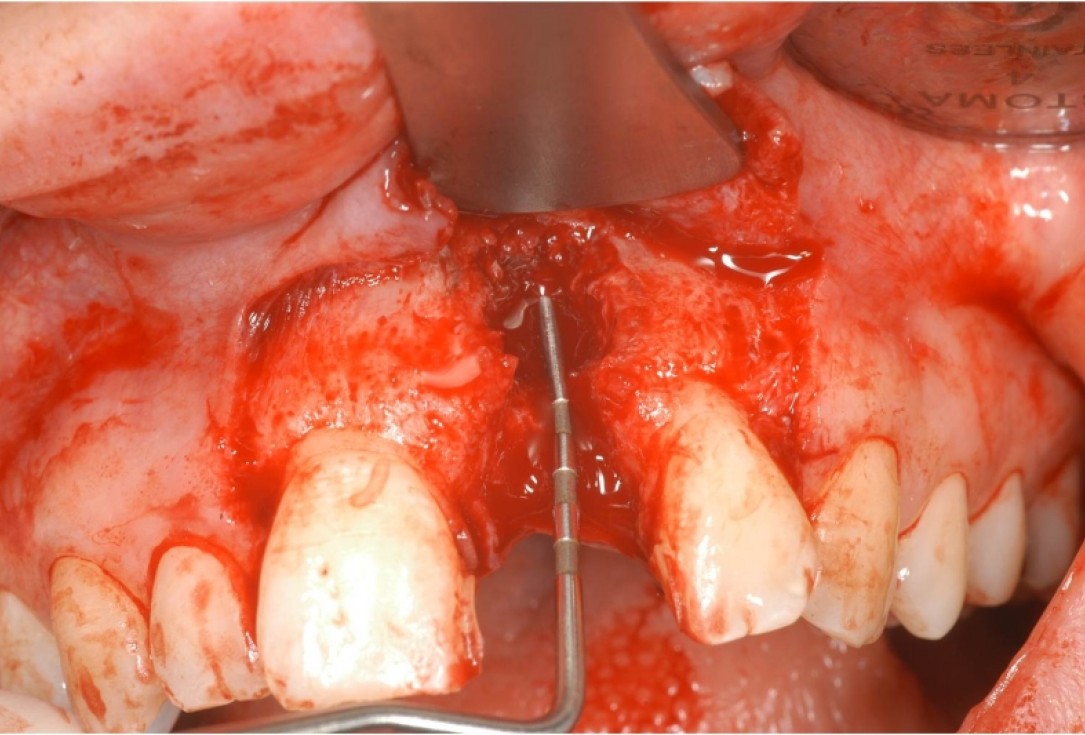

03/12 - Contained defect, boardered by mesiale and distal bone wallTreatment of dehiscence defect with cerabone® & Jason® membrane - Dr. M. Steigmann